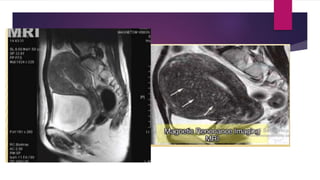

PRUEBAS DIAGNOSTICAS

 Histerosalpingografia:

Divertículos endometriales

y defectos en panal de abejas

 Ecografía:

 Estudio Ultrasonográfico Transvaginal

 Zonas anecogénicas tamaño variable Miometrial (aspecto quístico)

 Miometrio heterogéneo

 Vascularidad dispersa

 Aumento del tamaño uterino

 Sensibilidad 80%

 Especificidad 50%

 Ecografía:  EstudioUltrasonográfico Transvaginal  Zonas anecogénicas tamaño variable Miometrial (aspecto quístico)  Miometrio heterogéneo  Vascularidad dispersa  Aumento del tamaño uterino  Sensibilidad 80%  Especificidad 50%